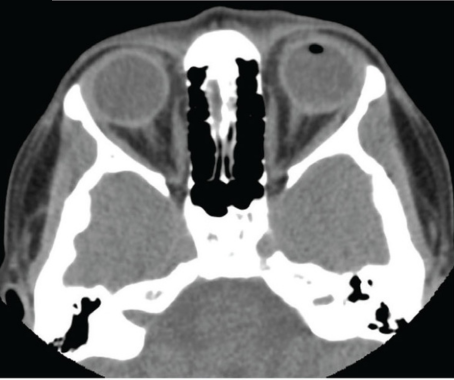

Autologous retinal transplantation is one surgical technique showing promise for large or recurrent macular holes, especially those >800 µm.